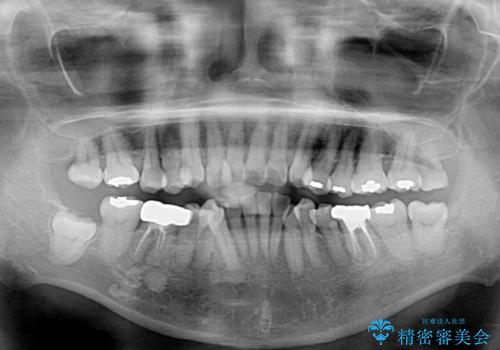

- 八重歯やクロスバイトを気にして来院された患者様です。

口元の突出感はありませんでしたが、デコボコが強く、非抜歯矯正とすると出っ歯仕上がりとなる可能性があったため、上下左右の第一小臼歯4本を抜歯し、ワイヤー装置にて矯正治療を行うこととしました。